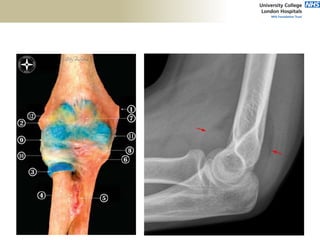

Proximal

Ulna

Diaphyseal

Angle

• Anterior offset of distal humerus

• Uniaxial hinge

• Carrying angle 11-14deg

• Axis: abducted by 50% of CA